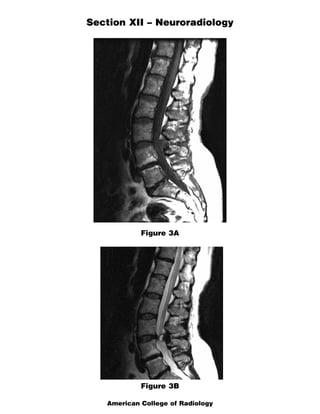

The document discusses several radiology cases involving the brain and spine. Question 291 presents CT scans of a woman with headaches and asks for the most likely diagnosis of a fat-containing extraconal orbital mass. Question 292 shows MR images of a woman with extremity weakness and asks for the most likely diagnosis of multiple brain and spine lesions. Question 293 presents MR images of a man with back pain and asks for the diagnosis of a posterior spinal mass seen on the images.